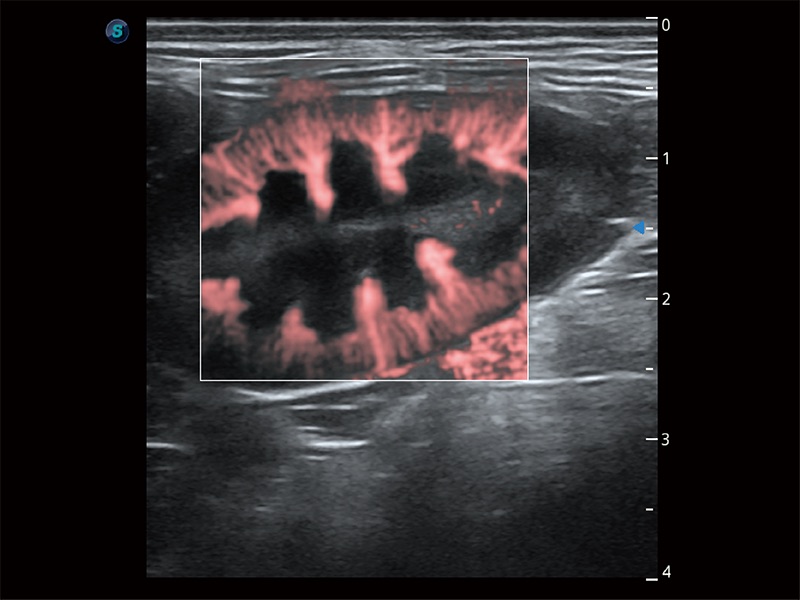

极大提升超低速微细血流的检出能力,同时更精准地滤除软组织和超声信号,为兽用医生提供以往无法通过常规血流获得的疾病诊断信息。

在传统二维血流成像的基础上,呈现血流的立体感,具有动感的生命力之美。即便是微小的血管也能轻松应对,提高了血流的视觉敏感性。

操作简便,无需高频度外力作用即可真实反映组织的形变,快速评估肿瘤良恶性。

非线性融合造影成像充分利用谐波和基波信号,为难以观察的血流进行增强显像。可用于线阵、凸阵、微凸阵、相控阵探头。